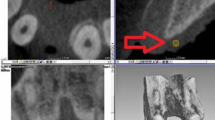

Purpose Medical imaging and in particular digital radiographic images offer a great deal of information to dentists in the clinical diagnosis and treatment processes on a daily basis. This paper presents a new method aimed to produce an accurate segmentation of dental implants and the crestal bone line in radiographic images. With this, it is possible computing several measures to biomechanical and clinical evaluation of dental implants positioning and evolution. Methods The proposed segmentation method includes two major steps: (1) the preprocessing that combine denoising filters, morphological operations and histogram threshold techniques and (2) the final segmentation involving made-to-measure adjusted and trained active shape models for detecting the precise location of the intended structures. Results Resulting measurements were compared to manual measurements made by experts on representative radiographs from patients. The calculated intraclass correlation coefficient was 0.75 and showed good reliability of the method, and the Bland-Altman analysis showed 95 % of the values within the limits of agreement. The mean of the differences between the manual and method-driven measurements was 0.049 mm (\(-0.137; -0.040\)) 95 % CI, inferior to the established limit (0.15mm). Conclusions It was demonstrated that the method achieved a precise segmentation of the intended structures. The validation process on standardized periapical radiographs showed good agreement between the manual measurements and the ones produced by the new method. Future work will be focused on making the method more robust to densitometry changes and to validate the method on non-standardized radiographs.